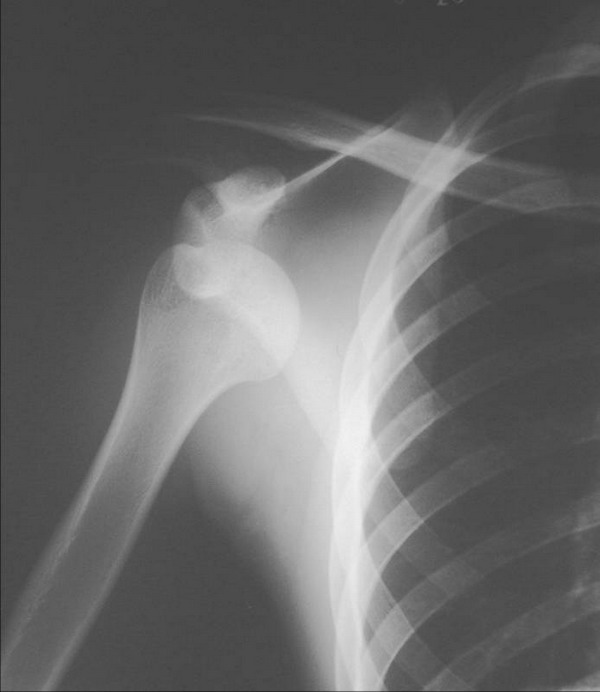

接下来来看手部当手的上臂受伤时有可能发生的骨折大家还记得吗是肱骨髁上骨折会有明显的肿胀畸形最特殊的是给大家介绍过的肘后三角关系,也就是肱骨内、外上髁和尺骨鹰嘴形成的三角形,因为骨头从肱骨的髁上断裂,而这三个部位没有发生改变,所以肘后三角关系是正常的。

上臂受伤和肱骨髁上骨折容易混淆的是肘关节脱位。肘关节脱位时,如果上臂是伸直手掌着地的,暴力传递到尺桡骨上端,尺骨鹰嘴突产生杠杆的作用,导致肘关节脱出。由于尺骨鹰嘴处发生了位移,导致失去肘后三角关系。从发生的人群来看,肘关节脱位多见于青壮年。